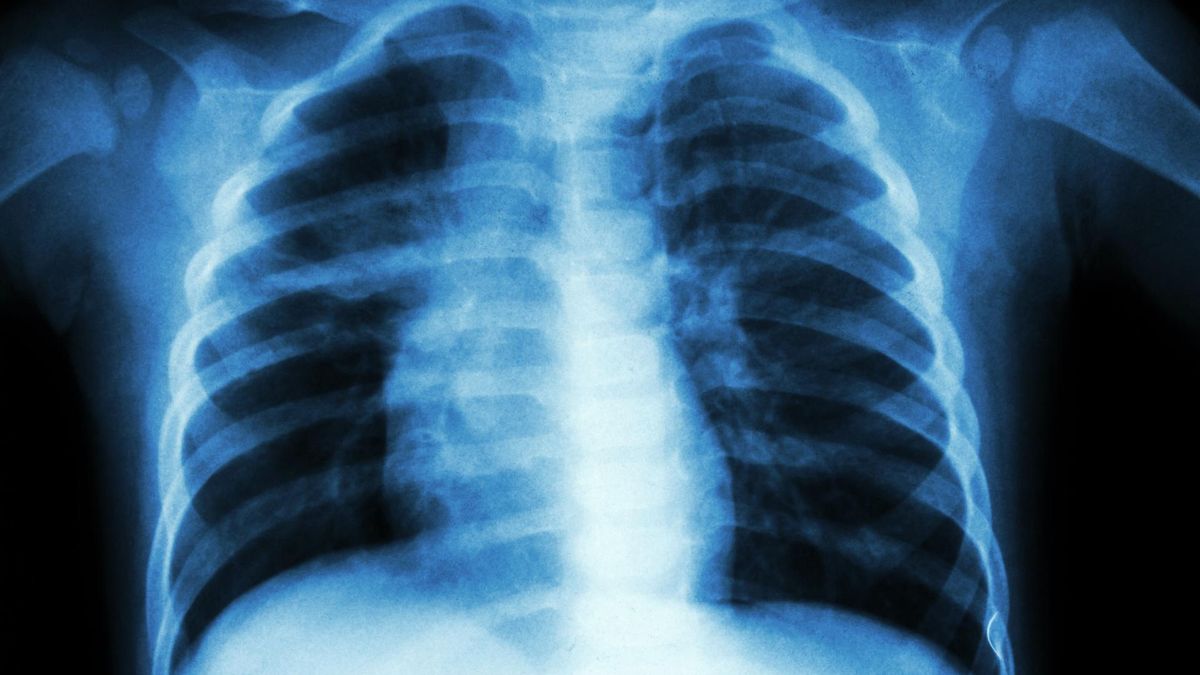

Rzucasz palenie? To świetnie. Pewnie jednak nie wiesz, że w zależności od tego, jak długo i jak wiele papierosów spalałeś w ciągu dnia, nikotyna i inne szkodliwe substancje mogą zalegać w twoich płucach nawet jeszcze przez kilka miesięcy. Ich obecność w organizmie może prowadzić do szeregu zaburzeń i chorób, takich jak np. zawał serca czy udar mózgu.

Źródło zdjęć: © (123rf.com) Nikotyna i inne szkodliwe substancje mogą zalegać w twoich płucach nawet przez kilka miesięcy